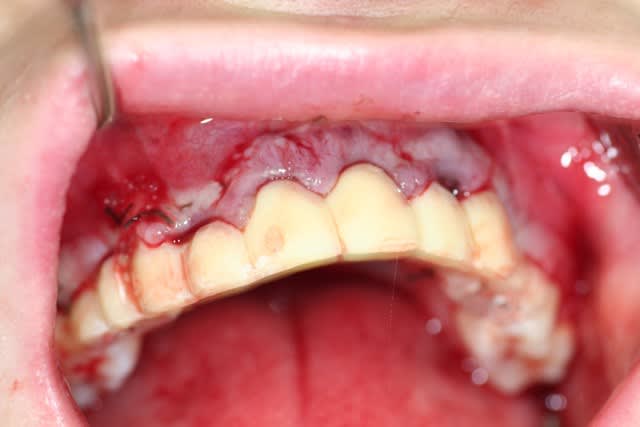

ok. traitement accepté par le patient.

finalement, j'ai décidé d'extraire les quatre incisives.

j'ai fait le pari de pouvoir mettre 6 direct abutments sur les implants pour faire un bridge scellé. ouf.....

désolé pour la qualité de l'image: nous n'étions que deux, et donc pas très simple....

la suite au fur et à mesure....

Extractions xag6t9 - Eugenol